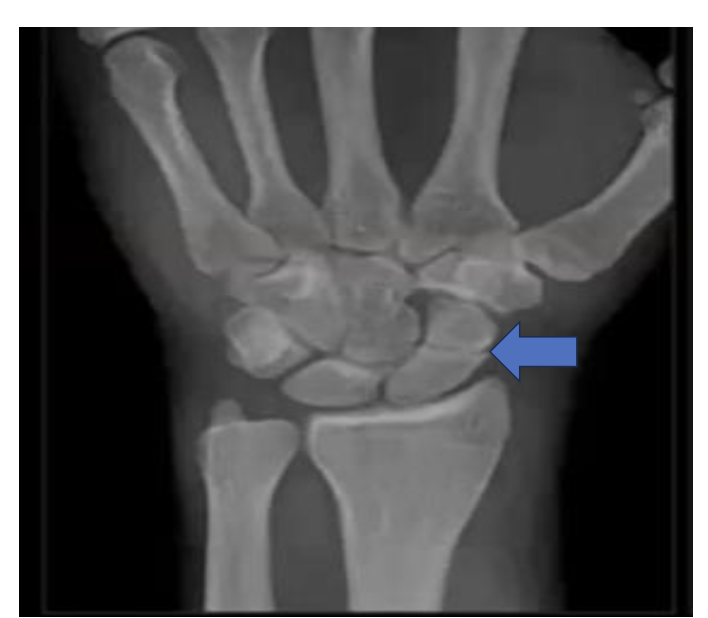

Identify the structures ? view? what joint ?

Wrist joint -AP

Scaphoid

Lunate

Triquetrum

Pisiform

Trapezium

Trapezoid

Capitate

Hamate